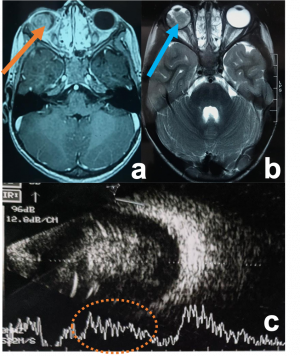

| Uveal Melanoma[45] | Middle aged adults | Dimunition of vision, assoicated with exudative retinal detachment. | MRI is the investigation of choice.

T1 hyperintensity T2- hypointense It enhances brightly on contrast |